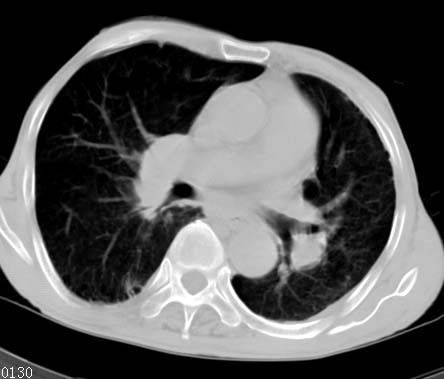

男性病人 81岁 胸痛 咳嗽2月 2周前提示右下肺感染.

今片ct示双肺多发结节影 可以这样诊断吗?1\双肺感染性病变 结核待排.

2\双肺纤维硬结灶,左肺肺气肿.

3\肺间质纤维化,胸膜肥厚粘连.

纵隔左移双肺上叶纤维硬结,肺气肿,双侧斑痕肺大泡,双侧胸膜增厚并胸膜下陈旧性病灶,右肺下叶胸膜下小结节影,密度较淡,建议复查.

病人桶状胸,胸廓肌肉消瘦;两上肺均可见纤维条索灶,下肺外围胸膜下可见间质纤维化改变,右下肺沿肺纹理分部结节样病灶,边缘光滑,考虑1、慢支并局灶性间质纤维化、右下肺合并感染,2、两上肺为陈旧性肺结核灶并瘢痕旁型肺气肿3、右下肺转移瘤待排。

两肺上叶见多发索条状高密度影,右肺下叶见片状、结节状高密度影,两肺体积增大,胸膜下区见囊状低密度影、内有分隔结构。左肺下叶见网格影。两侧胸膜见增厚影。诊断:两肺继发性肺结核。慢性支气管炎合并感染。肺气肿。肺间质纤维化。胸膜增厚。